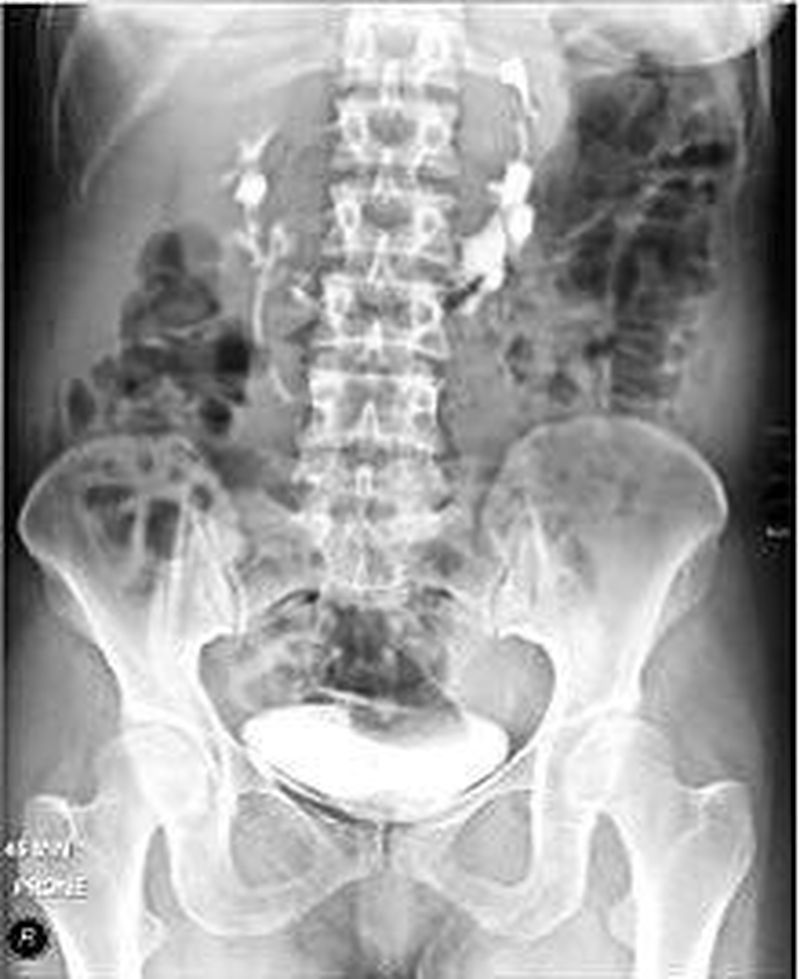

Intravenous pyelogram showing horseshoe kidney.

In this disorder, the patient's kidneys fuse together to form a horseshoe-shape during development in the womb. The fused part is the isthmus of the horseshoe kidney. The abnormal anatomy can affect kidney drainage resulting increased frequency of kidney stones and urinary tract infections as well as increase risk of certain renal cancers.